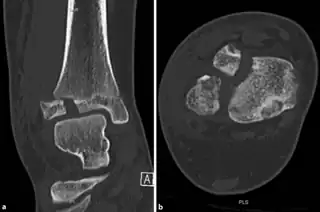

- CT scan

a,b)CT scan, coronal and axial plane of a Tillaux fracture in a male